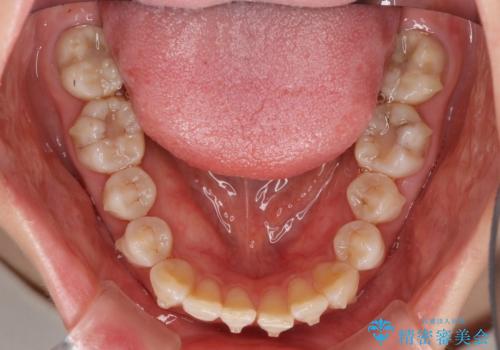

話しにくいオープンバイト インビザラインによる矯正治療

- 前歯の上下スペースによる話しにくさを気にして来院された患者様です。

インビザラインにより上下の前歯の隙間を閉じていくこととしました。

上下の奥歯を圧下させるようにすることで、前歯を接触させるように計画しました。

隙間に舌が入り込むことが話しにくさに繋がっていたため、舌の筋肉のトレーニングも並行して行い、話しにくさの改善と後戻りの抑制を図りました。